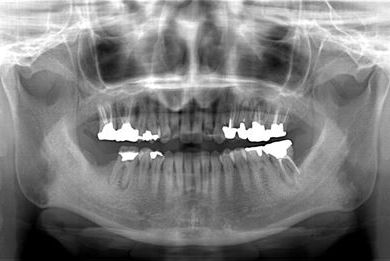

治療前

• 治療前